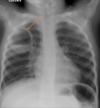

12

Q

A

Consolidación alveolar